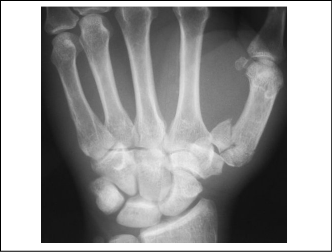

The Bennett fracture, Rolando fracture, and skier’s thumb all present with pincer grasp weakness. However, the injuries may be differentiated by the location of tenderness. Skier’s thumb (UCL tear) is characterized by point tenderness and instability at the thumb MCP joint, while a Bennett or Rolando fracture involves only the CMC joint. As with the evaluation of other thumb injuries, radiographs should be obtained of the patient suspected to have a skier’s thumb. It is important to remember that a skier’s thumb may or may not be visible on X-ray, and the most common radiographic finding is an avulsion fracture of the proximal thumb phalanx at the site of UCL attachment. (See Figure 6.) A Stener lesion is a particular type of UCL injury with palmar subluxation of the base of the proximal phalanx.17 A skier’s thumb should be repaired by an orthopedic and/or hand specialist within one week if the UCL tear is complete. Incomplete tears may need physical therapy and rehabilitation. In either case, ED treatment includes immobilization with a thumb spica splint or cast and subspecialty referral within 2-3 days.

Figure 6. Radiograph of Skier’s Thumb